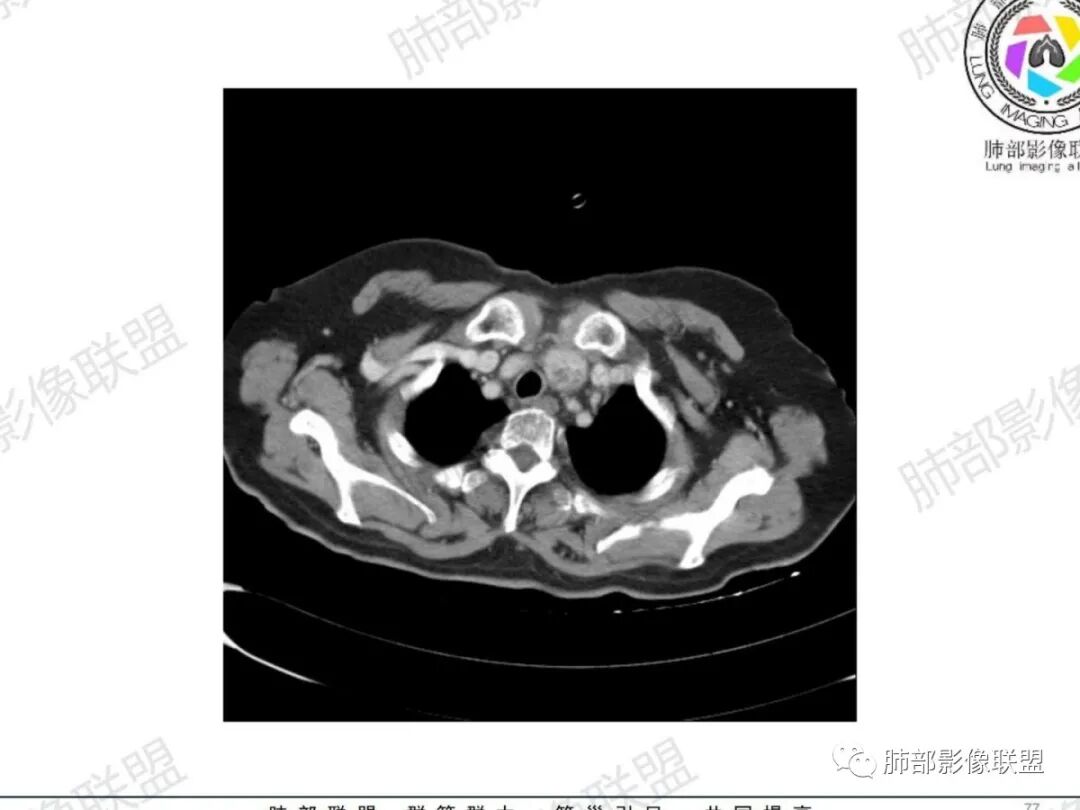

主支气管后缘外可见一实性结节,病变跨支气管管壁生长,部分突向管腔内,病变边缘光滑,平扫密度均匀,增强后尚均匀强化,纵隔淋巴结肿大不明显。

气管右后侧壁结节,结节向气管腔内突出,气管壁增厚,轻度强化,左侧甲状腺占位,考虑气管原发肿瘤,腺样囊性癌?类癌?

女,69反复咳嗽1年,胸闷二天,气管腔内见结节影,病灶突向腔内,管腔狭窄受压呈月牙状改变,增强扫描轻度强化,考虑腺癌?左侧甲状腺病变,不除外转移性病变。

气管右后壁占位,平扫密度稍低于肌肉

增强后与肌肉类似,部分强于肌肉,提示强化

内外边缘光滑

宽基底与气管相连

附近壁增厚

前方见一小淋巴结,后内侧与食道联系很紧